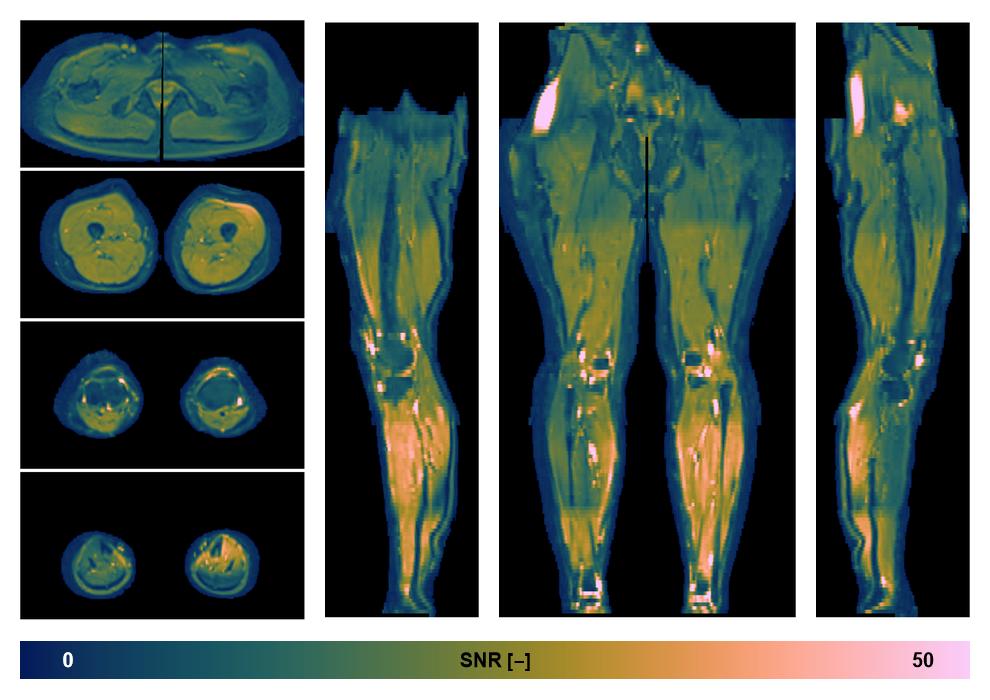

• SNR distribution

The SNR distribution of the dixon data.